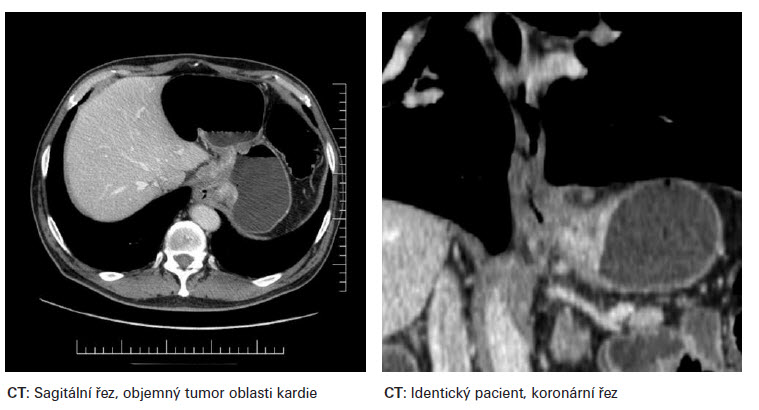

Strategie léčby adenokarcinomu oblasti EGJ je dána stadiem onemocnění. Toto je určeno nadále exaktním stanovením TNM parametrů. Diagnostika parametru T se opírá o CT,GF a též o endosonografický nález. Diagnostika N stadia, využívá dále i PET a FNB. Možná je i laparoskopická diagnostika, výjimečně VATS (videotorakoskopie). K chirurgické léčbě je určeno primárně stadium I. a II. U stadia II. je indikovaná pooperační adjuvantní chemoterapie u high risk T2N0 - v případě G3, lymfovaskulární invaze, neurovaskulární invaze a mladého věku pacientů. Dále v případě T3N0, T1-2 N1. Možná je i perioperační chemoterapie ECF (3 cykly před operací, 3 cykly po operaci). Stadium III. je indikované k chirurgické léčbě v případě dobré odpovědi na neoadjuantní onkoterapii. Neoadjuvantní léčba zvyšuje počet radikálních operací. Onkologická léčba po chirurgickém resekčním výkonu je dále též korigovaná typem resekce - R0, R1 a definitivním pTpNpM. Typ resekčního výkonu můžeme stanovit pomocí Siewertova doporučení, klasifikace adenokarcinomu oblasti EGJ.

Siewertova klasifikace adenokarcinomu lokalizovaného v oblasti kardie (Siewet et. al 1987 Mnichov) dělí tumory do tří typů. Typ I. - centrum tumoru leží 1-5cm orálně od EGJ. Typ II. - centrum tumoru infiltruje EGJ, tumor je lokalizovaný od 1 cm orálně až 2 cm aborálně od junkce. Typ III. - centrum tumoru je lokalizovano 2-5 cm pod EGJ. Dle Siewertovy klasifikace, je pak stanoven typ chirurgického resekčního výkonu. Pro typ I. se jedná o subtotální esofagektomii s proximální resekcí žaludku s lymfadenektomií paraezofageální a horního břišní kompartmentu. K obnovení kontinuity zažívacího traktu je možno využít gastropastiku zbylé části žaludku (velká křivina, antrum) či interpozitum kličkou jejuna dle Rouxe či koloplastiku. Pro typ II. a III. je indikována totální gastrektomie s distální resekcí jícnu a lymfadenektomií dolního mediastina s D2 břišní lymfadenektomií. Obnovení zažívacího traktu je konstruováno zpravidla jejunoplastikou. Součástí chirurgických resekčních výkonů je i omentektomie. V literatuře je možno se setkat i s „maximálním" resekčním výkonem typu totální gastrektomie se subtotální ezofagektomií s koloplastikou. Výkon je ale zpravidla zatížen vysokou morbididou doprovázenou i vyšší mortalitou. Invaze tumoru do bránice, jater - T4 v případě N0-1, za předpokladu případné resekability R0, není po neoadjuvantní léčbě s dobou odpovědí kontraindikací k chirurgické léčbě. V případě totální gastrektomie provádíme lymfadenektomii typu D2, lymfadenektomii D1 nepovažujeme za dostatečnou. Evropskými autory popisovaná vyšší morbidita i mortalita spojena s lymfadenektomií typu D2 je dána předně technickou peroperační komplikací, při které dochází ke krvácení a vynuceně ke splenektomii či resekci pankreatu, které nejsou běžnou součástí chirurgické léčby. Zásadní je lymfadenektomie v bezprostředním okolí tumoru, kompletní resekce malého omenta a lymfadnektomie oblasti a. gastrica sinistra a trunkus celiakus. S paraezofageální lymfadenektomií a lymfadenektomií oblasti bifurkace trachei nebývají zpravidla technické potíže. Spádové lymfatické uzliny žaludku dělíme dle modifikované klasifikace dle JRSGC (Japanese Research Society for Gastric Cancer) do tří kompartementů. Lymfatické uzliny stanice 1.-6. tvoří I., 7.-11. II. a 12.-16. III. kompartment. Dle některých autorů tvoří LU skupiny 15. a 16. kompartement IV. Lymfadenektomie typu D1 spočívá v odstranění uzlin a přilehlé tukové tkáně kompartmentu I., D 2 I. a II. Dle TNM klasifikace tvoří metastázy v LU III. kompartementu marker M1. Skupiny lymfatických uzlin dle stanic: 1. parakardiální při malé křivině, 2. parakardiální při velké křivině, 3. uzliny podél malého zakřivení žaludku, 4. podél velkého zakřivení, 5. podél suprapylorické, 6. infrapylorické, 7. uzliny podél a. gastrica sinistra, 8. podél a. hepatica communis, 9. v oblasti truncus coeliacus, 10. v oblasti hilu sleziny, 11. podél av. lienalis, 12. oblast ligamentum hepato-duodenale, 13. retropankreaticky v oblasti hlavy slinivky břišní, 14. podél av. mesenterica superior, 15. podél av. colica media, 16. podél abdominální aorty.